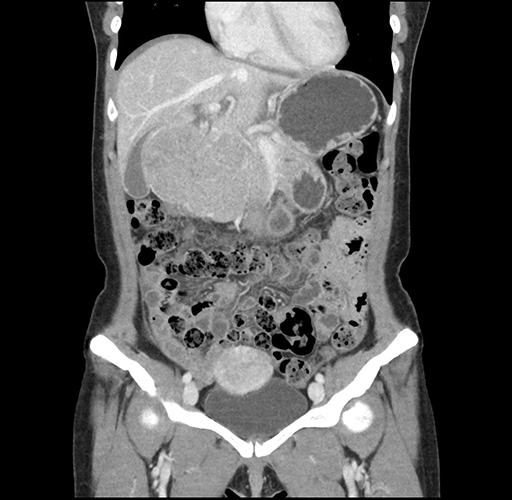

Imaging Analysis

Look through the patient's CT scan to identify any areas of concern for the necessary procedure.

Based on your CT findings, which issue(s) would give reason for "planned slowing down moment(s)" in this case?

Considering a standard left lateral sectionectomy procedure, what step(s) of the operation would you do differently in this case ?